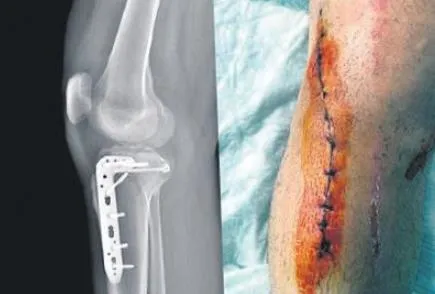

İstanbul'da avukat Fatih Uzun, 22 Nisan'da ailesiyle Manisa'dan İstanbul'a dönerken birbirini sollayan ünlü araç ve Ford Focus marka araçların tehlikeli sürüşünden kaçmak için şerit değiştirmek istedi. Lüks araç sürücüsü olan Muğla'da görevli polis memuru Hüseyin Tayfun Üçgül, kendisini sollayan Uzun'un aracını sıkıştırarak taciz etti. Avukata küfürler ederek aracı durdurmasını isteyen polis memuru, trafikte adeta terör estirdi. Uzun'un aracının önüne geçip fren yapan polis, avukatın bacağının iki yerden kırılmasına yol açtı.